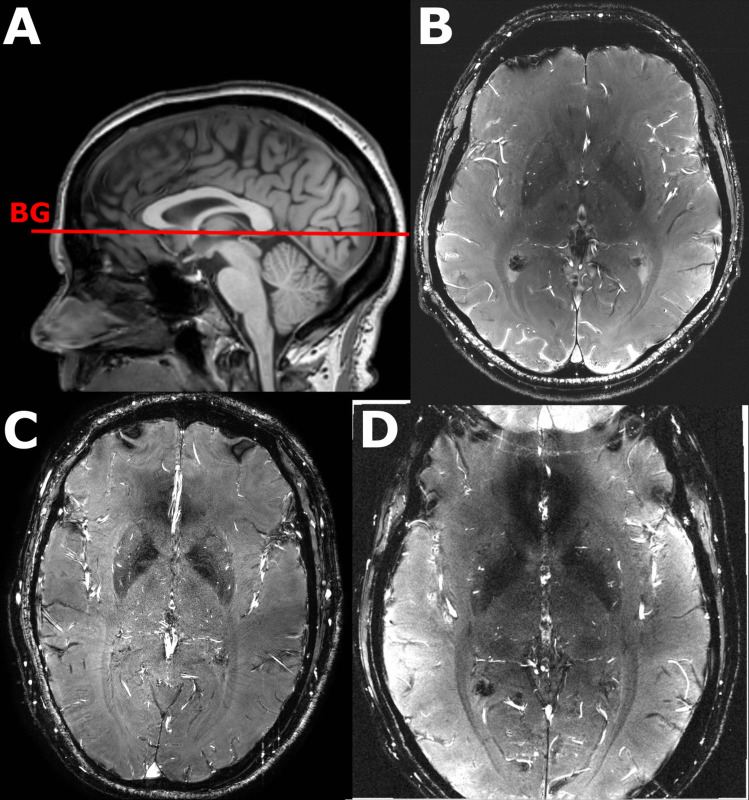

在二维平面上,通过相衬磁成像(2D PC-MRI)可以量化脑穿动脉的血流速度。速度脉搏指数(PI)可以反映这些穿孔动脉的僵硬程度,这与几种脑血管疾病有关。目前,还没有针对这些小血管的2D PC-MRI数据的开源分析工具,阻碍了这些测量的使用。在这项研究中,我们提出了小血管标记(SELMA)分析软件,作为一种新颖的、用户友好的、开源的工具,用于分析脑穿孔动脉的流速。SELMA中分析算法的实现通过Bland-Altman分析对先前发表的数据进行了验证。SELMA的评分间信度评估了来自八个不同地点的三个MRI供应商的60名参与者的PC-MRI数据。SELMA的平均速度(vmean)和速度PI与原始结果非常相似(vmean:平均差±标准差:0.1±0.8 cm/s;速度PI:平均差值±标准差:0.01±0.1),而SELMA检测到的血管数量略高(未检测到的血管数量:平均差值±标准差:4±9),这可以用SELMA的血管选择范式来解释。使用SELMA的两个操作符之间绘制的感兴趣区域的骰子相似系数为0.91(范围为0.69-0.95),Ndetected, vmean和速度PI的总体类内系数分别为0.92,0.84和0.85。结果测量在不同地点之间的差异大于供应商之间的差异,这表明在协调2D PC-MRI序列方面存在挑战,即使是在同一供应商的不同地点。我们表明SELMA是一个一致的和用户友好的小脑血管分析工具。

Blood flow velocity in the cerebral perforating arteries can be quantified in a two-dimensional plane with phase contrast magnetic imaging (2D PC-MRI). The velocity pulsatility index (PI) can inform on the stiffness of these perforating arteries, which is related to several cerebrovascular diseases. Currently, there is no open-source analysis tool for 2D PC-MRI data from these small vessels, impeding the usage of these measurements. In this study we present the Small vessEL MArker (SELMA) analysis software as a novel, user-friendly, open-source tool for velocity analysis in cerebral perforating arteries. The implementation of the analysis algorithm in SELMA was validated against previously published data with a Bland-Altman analysis. The inter-rater reliability of SELMA was assessed on PC-MRI data of sixty participants from three MRI vendors between eight different sites. The mean velocity (vmean) and velocity PI of SELMA was very similar to the original results (vmean: mean difference ± standard deviation: 0.1 ± 0.8 cm/s; velocity PI: mean difference ± standard deviation: 0.01 ± 0.1) despite the slightly higher number of detected vessels in SELMA (Ndetected: mean difference ± standard deviation: 4 ± 9 vessels), which can be explained by the vessel selection paradigm of SELMA. The Dice Similarity Coefficient of drawn regions of interest between two operators using SELMA was 0.91 (range 0.69-0.95) and the overall intra-class coefficient for Ndetected, vmean, and velocity PI were 0.92, 0.84, and 0.85, respectively. The differences in the outcome measures was higher between sites than vendors, indicating the challenges in harmonizing the 2D PC-MRI sequence even across sites with the same vendor. We show that SELMA is a consistent and user-friendly analysis tool for small cerebral vessels.